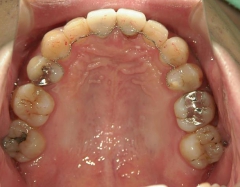

矯正歯科 治療後矯正歯科 全顎ワイヤー矯正 治療後矯正歯科(全顎ワイヤー矯正)治療後

矯正歯科 治療後 E-AMXというセラミックにて左右上1番を被せ直しました。

矯正_灰色.pngno.24_8228_治療後_上.jpg矯正_灰色.png